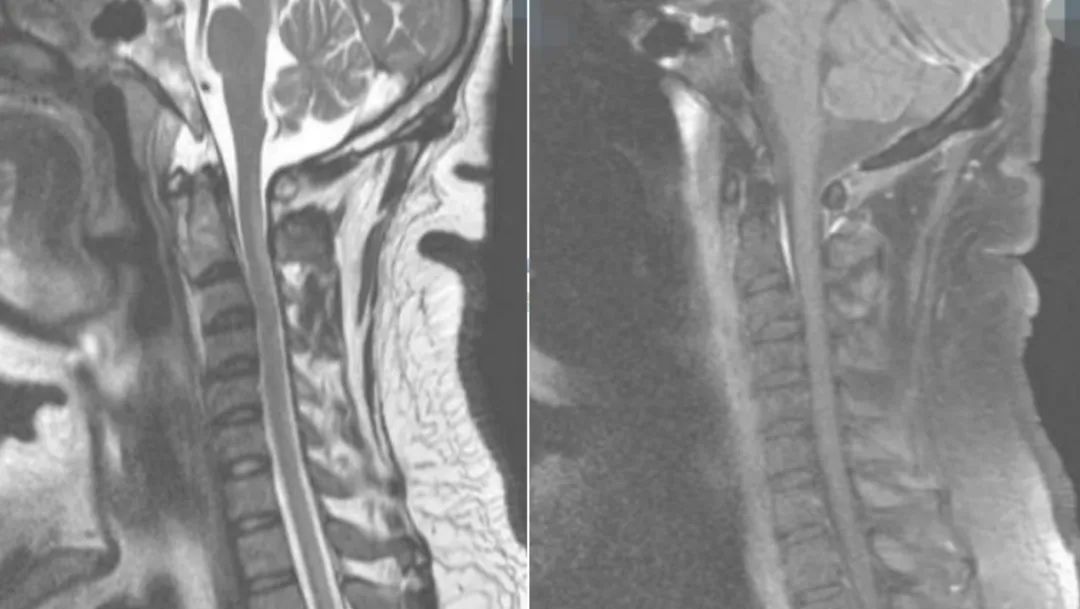

老年女性,急性起病,突发颈后部疼痛伴右侧肢体麻木无力,右侧肢体肌力2级。

答案:脊髓硬膜外血肿。补充病史既往长期服用华法林。患者临床以麻木,肢体无力卒中样起病。但是有颈部疼痛病史,病史跟影像提示脊髓硬膜外血肿。脊髓硬膜外血肿可能是自发的,也可能是继发于创伤、凝血功能障碍或麻醉操作。危险因素包括高龄、女性、创伤、血管畸形、抗凝治疗和高血压。提醒注意的是这样的患者有可能在绿色通道中被当做急性卒中患者被溶栓。